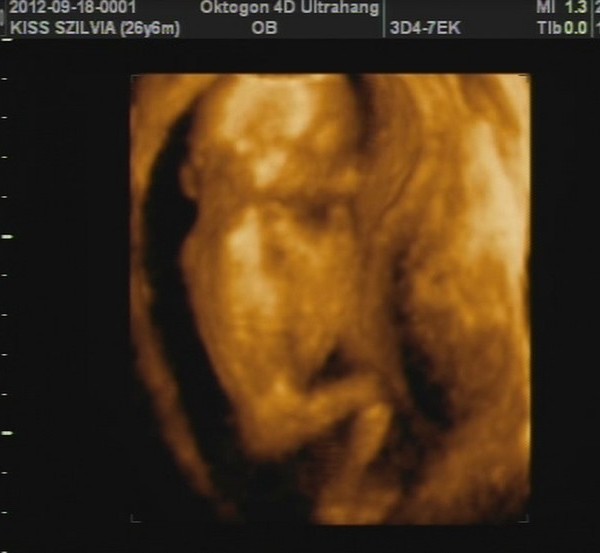

A képek először a babáról. :-) Kép 4d kedvenc :-)

Kép és ott az a pici háromszög a lábikó között a kukac :-)

Sziszianyu de édes ez a baba :D :D :D Hogy bebújt a méhlepénybe:-))) a tappancsos kép is nagyon aranyos:-))))